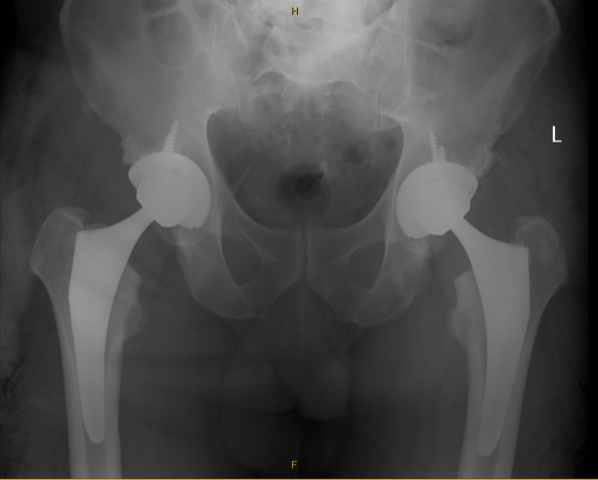

Total Hip Replacement (THR)

Minimally invasive and muscle-sparing direct anterior approaches

Revision surgery for previously replaced hips

Computer-navigated and robotic-assisted techniques

The goal is to reduce pain, restore motion, and help you return to the activities you enjoy.

Hip pain and stiffness from arthritis or injury can make walking, sleeping, and everyday activities a struggle. Professor Tran offers hip replacement surgery using modern techniques that minimise tissue disruption and support faster recovery.